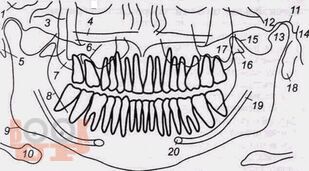

В учебно-методическом пособии представлен доступный алгоритм лучевой диагностики при синдроме болевой дисфункции височно-нижнечелюстного сустава. Алгоритм дает возможность повысить точность диагностики, а следовательно, и эффективность лечения пациентов, индивидуализировать методы терапии каждого больного.

Пособие предназначено для врачей разных специальностей: стоматологов, неврологов и рентгенологов, а также интернов и ординаторов.